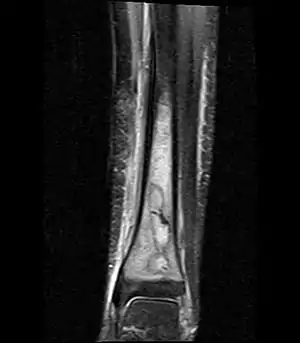

| یک تصویر امآرآی از آبسه برودی در پایین درشتنی | |

این آبسه در رادیولوژی به صورت یک ضایعه لیتیک یا شفاف (رادیولوسنت) که بیضی شکل یا گرد است و معمولاً بزرگتر از یک سانت میباشد و دارای حاشیه سختاک میباشد، دیده میشود. سیتی اسکن بهترین روش تشخیص آبسه برودی است.